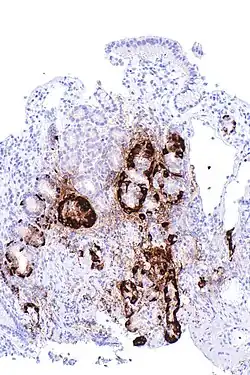

Micrograph showing nodular enterochromaffin-like cell hyperplasia, as demonstrated with chromogranin A immunostaining, in the body of the stomach. Parietal cells are not readily apparent. These changes are in keeping with autoimmune metaplastic atrophic gastritis, a histologic correlate of vitamin B12 deficiency anemia. | |